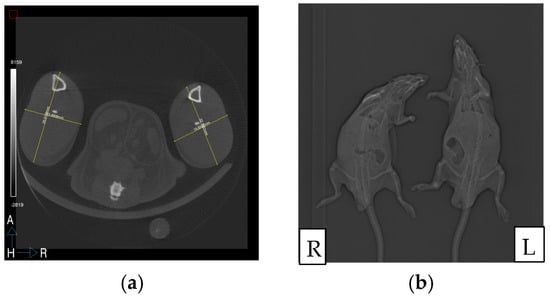

2.2. Limb Volume Calculation

3.1. Limb Volume Calculation